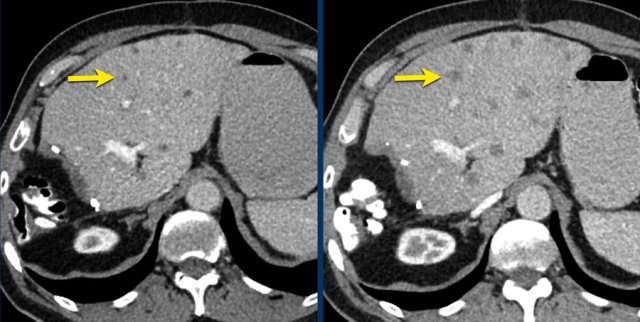

The CT images in a 66-year-old male show liver metastases of a GIST at diagnosis (a).

At 3 months after treatment with imatinib there is a good response (b).

At a follow up scan at 1 year there is a  recurrence (arrow in c).

At a  follow-up after 2nd line treatment with sunitinib there is still tumor progression, but the size remains the same (d).